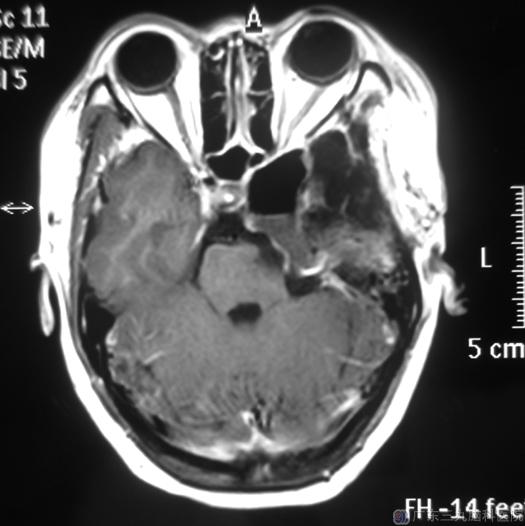

半年前,严姐的面部麻木以及眼部发作性抽搐等症状逐渐加重。去年10月在陪同表妹来广东三九脑科医院治疗的时候,听从医生的建议顺便复查了一下,结果显示:左侧中后颅窝占位性病变,考虑胆脂瘤复发,大小为:5.9cm×4.0cm×4.1cm。

讨论病情后,由鲁明主任主刀在全麻下硬脑膜外入路行左侧中后颅窝复发胆脂瘤切除术。术中见硬脑膜下有黄白色肿瘤组织,质地疏松。术后,麻木感较前减轻,她的左侧眼睛充血以及眼球运动也基本恢复正常。